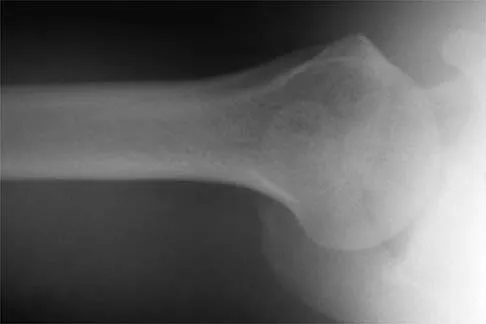

A 24-year-old runner who underwent an allograft reconstruction of the anterior cruciate ligament (ACL) 3 years ago now reports anterior knee pain. Examination reveals no swelling or effusion, and the patient has full motion. A Lachman test and a pivot-shift test are negative. Palpation reveals tenderness on the patellar tendon and at the inferior pole of the patella. AP and lateral radiographs are shown in Figures 41a and 41b. Management should consist of

Explanation